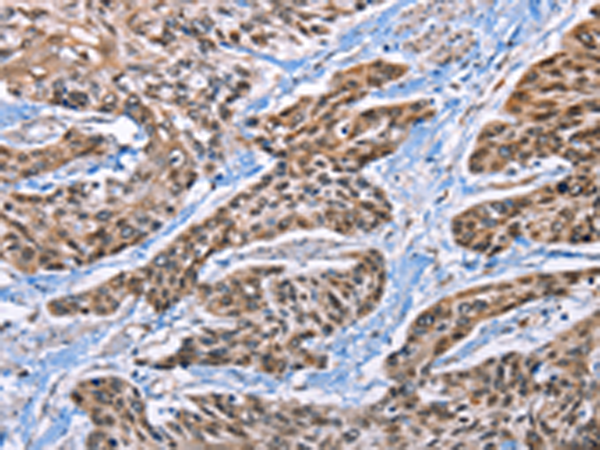

分类: 科研抗体货号: P04027别名: HMG-R, HMGIY, HMGA1A应用: IHC反应种属: Human, Mouse, Rat